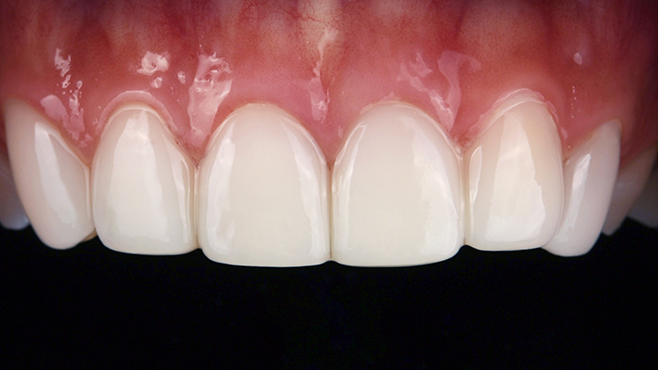

치과가 무서워 10년 동안 미뤄온 임플란트 수술 그 결과는?